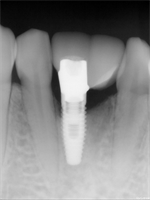

What to do when you only have room for one implant?

In this situation, the patient had two primary teeth in the anterior mandible that had a poor five year prognosis. The two teeth were extracted and I decided to place one NP Nobel implant and cantilever the restoration. I only had room for one NP implant. Would you treat the same way, or place...  Read More